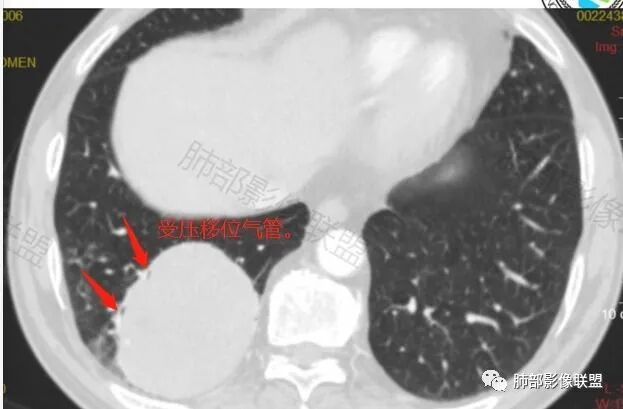

应该是气管

还是支气管

含气组织

受压推移

常规肿瘤如果背侧胸膜来源,肿瘤与胸膜之间不应该夹杂含气支气管,会推移

但是肺内可以将支气管外推,夹在胸膜之间

与膈面胸膜类似推断

支持肺内